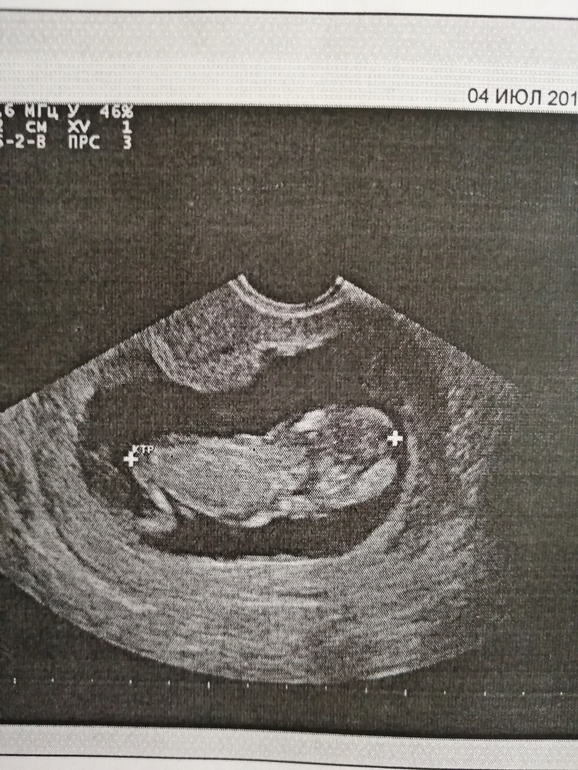

Добрый вечер мамуськи) сделала и я сегодня долгожданный 1 скрининг. Ура)) 12 нед. и 5 дней. ПДР 11 января 2020г. Вес 55 г. Женщина которая делала УЗИ, мне не очень понравилась, слова не вытянишь. Я как и многие тут не понимаю снимки, точнее не вижу кто, мальчик или девочка)) Но знаю точно, что в группе есть девочки которые понимают. Помогите понять пожалуйста)) кого вы видите.

По 1му фото предположу пацана. Но не факт. На остальных вообще ниче не видно.

На фото к сожалению не видно бугорка. Поздравляю с удачным скринингом. А кровь скоро будет готова? Сколько делают. У нас через неделю скрининг.

К сожалению полового бугорка не видно (

Может ещё фото есть ?